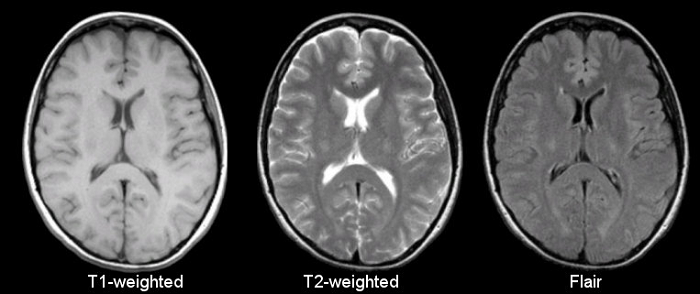

1503883475(1).jpg

脑医生系统标注的图像

如上图所示,红色的区域是大脑皮层灰质,这个区域的萎缩是阿尔兹海默症患者重要的早期诊断指标。脑医生系统通过自动标注受试者大脑重要结构的体积与正常指标作对比就可以对受试者情况作出判断

王思伦表示,现阶段脑医生最后给出的诊断报告就像我们平时感冒血常规化验单:白细胞总数12.2(正常5-12),中性粒细胞8.6(正常2-7.8),淋巴细胞比例17.9(正常20-40)……诊断报告标包含大脑重要结构的数据,包括脑灰质白质体积,海马结构及全脑45个重要分区的指标,医生一眼就可以看明白,并给出结论。拿到CFDA认证以后,脑医生会推出带有结论的诊断报告,供医生参考